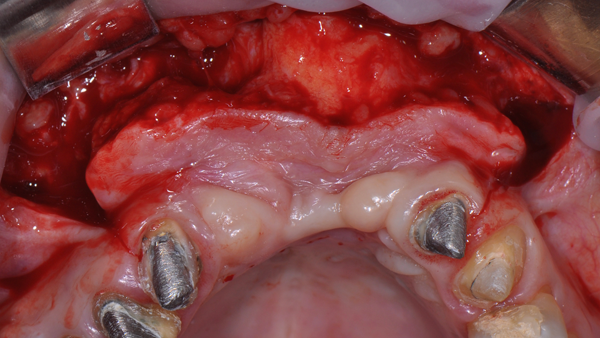

O enxerto ósseo heterógeno foi acomodado no leito receptor e coberto com a membrana Cytoplast reforçada com titânio (Figura 8), que foi estabilizada com parafusos de fixação (Kit GBR, NeoBiotech), Figura 9.

Uma vez que a membrana foi completamente fixada, o retalho foi mobilizado para permitir o fechamento primário livre de tensão. O retalho foi suturado em duas camadas: primeiro, as suturas horizontais em colchoeiro e, depois, as suturas simples para fechar as bordas do retalho (Figura 10). As suturas simples foram removidas 14 dias após a cirurgia e as suturas em colchoeiro horizontais foram removidas três semanas mais tarde. A membrana foi então removida após 25 semanas de cicatrização usando um retalho crestal de espessura total (Figuras 11 a 14).